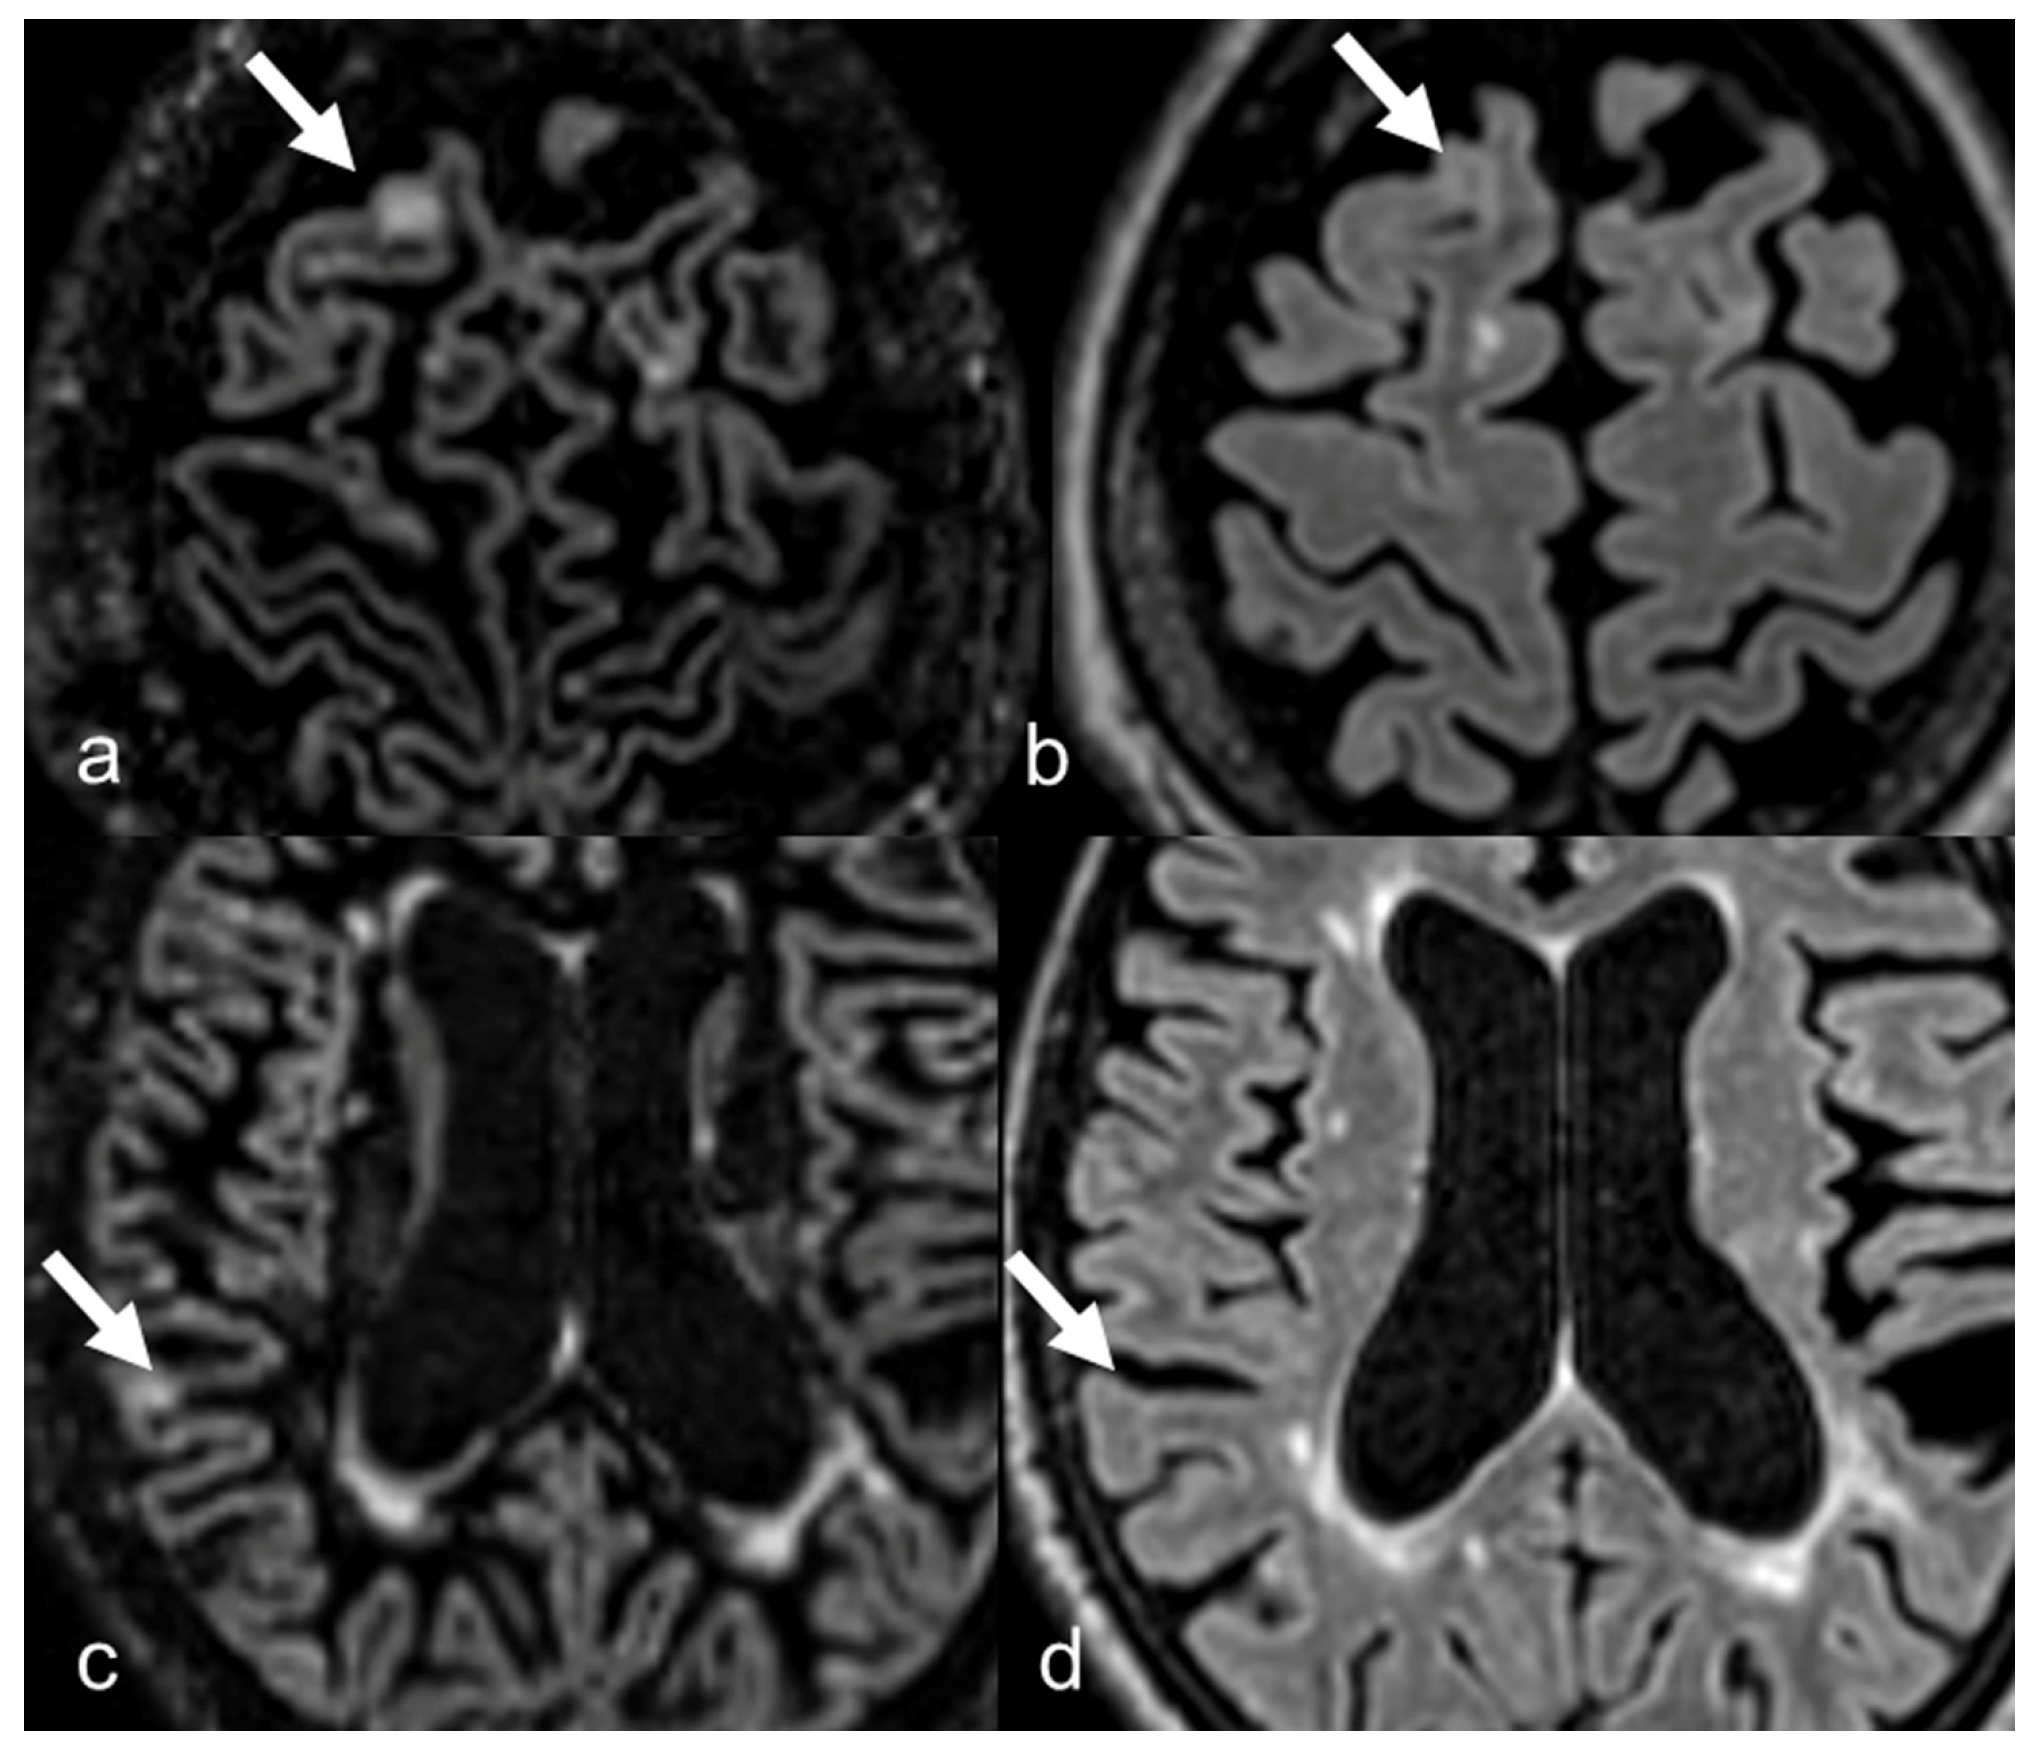

| In MS protocol, attention has to be paid to perform DIR before contrast-administration, as post-contrast DIR may suppress active subcortical lesions. |